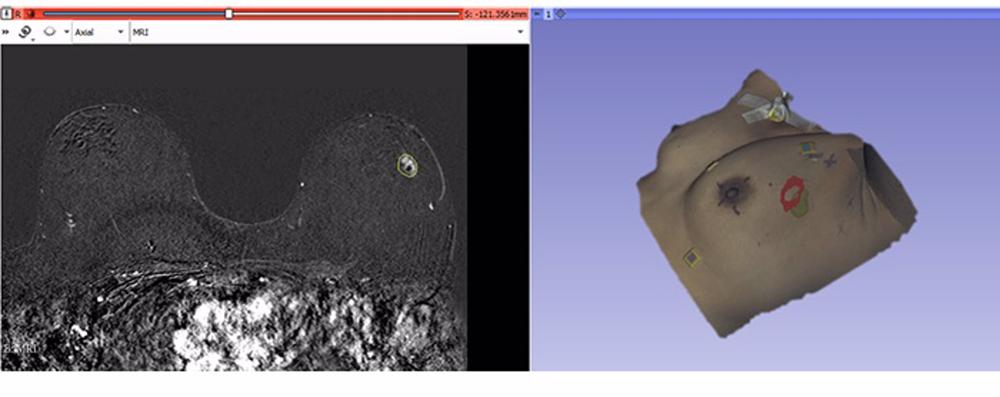

El nuevo método combina la información de la imagen preoperatoria con la de la superficie de la paciente, adquirida en el quirófano utilizando un escáner óptico, y así se consigue determinar la posición del tumor en la posición de la cirugía.

Los resultados obtenidos, usando datos de casos clínicos, muestran la posibilidad de obtener una localización precisa del tumor a partir de una sola imagen preoperatoria y de la superficie de la paciente adquirida en la posición quirúrgica, ’’alternando mínimamente el protocolo preoperatorio’’.

La técnica se ha implementado para su inclusión en una herramienta capaz de presentar al cirujano la escena intraoperatoria con modelos tridimensionales de la superficie y de la lesión, así como su proyección en la piel.